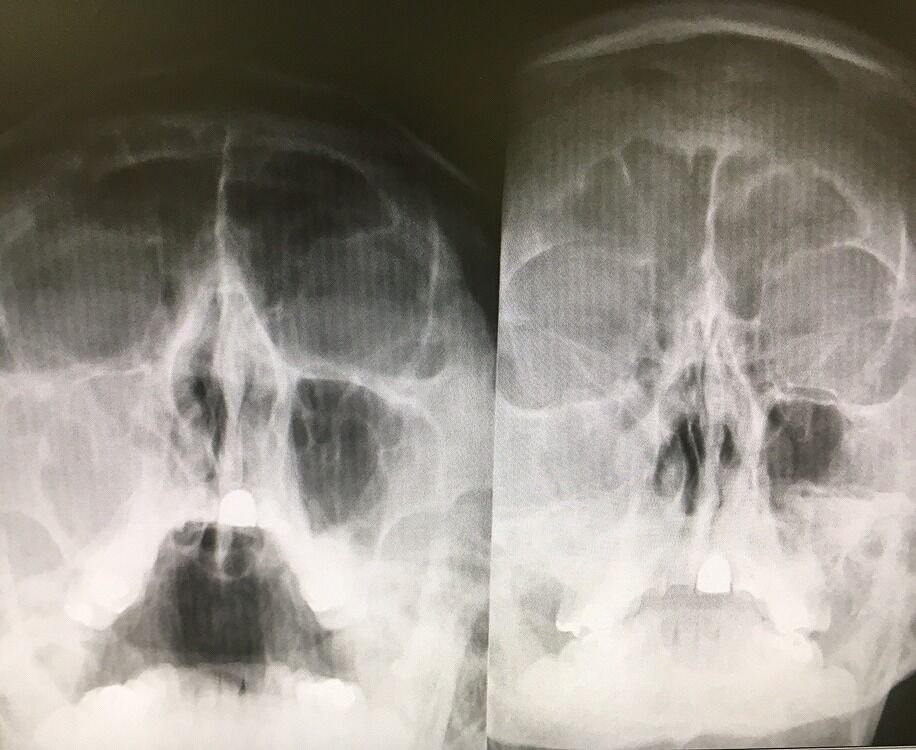

キレイな副鼻腔炎(蓄膿症)のレントゲン写真。

一カ月経っても、副鼻腔炎(蓄膿症)改善せず。